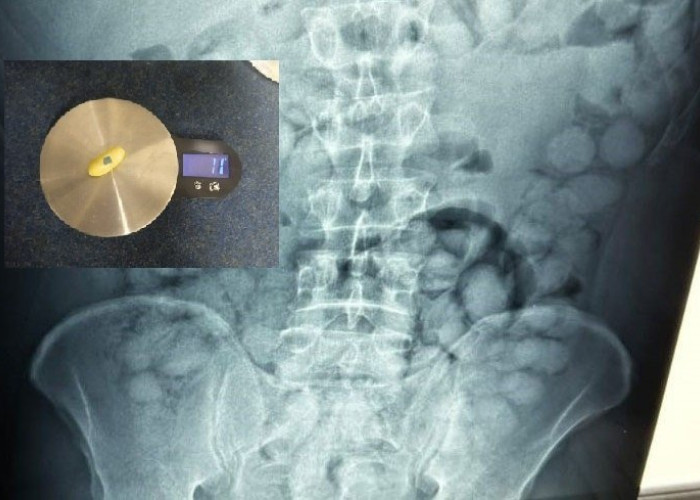

Επικαιρότητα Συνελήφθη Βραζιλιάνος στο «Ελ. Βενιζέλος» για διακίνηση ναρκωτικών – Είχε καταπιεί 100 «αυγά» κοκαΐνης 19 Αυγ 2025, 18:12